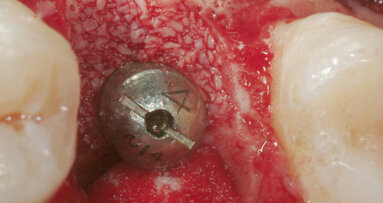

È stato inserito un impianto Straumann BLX 3.75 mm di diametro per 12 mm di lunghezza, con superficie SLActive seguendo l’asse protesico ideale (Figg. 4, 5). Avendo conseguito una stabilità primaria eccedente i 35 N/cm è stato realizzato un restauro provvisorio avvitato in composito su componente in Titanio da provvisori. Nonostante una sostanziale congruità della forma del provvisorio con la parte superficiale dell’alveolo, è stata utilizzata una matrice dermica suina (Botiss Mucoderm) allo scopo di sigillare il gap presente tra provvisorio e bordo mucoso dell’alveolo. Tale matrice, opportunamente sagomata e forata in modo da essere stabilizzata dal provvisorio stesso, è stata posizionata in modo da non rimanere esposta al cavo orale. Non sono state necessarie suture (Figg. 6-8).

Fig. 5_Rx periapicale post-impianto.